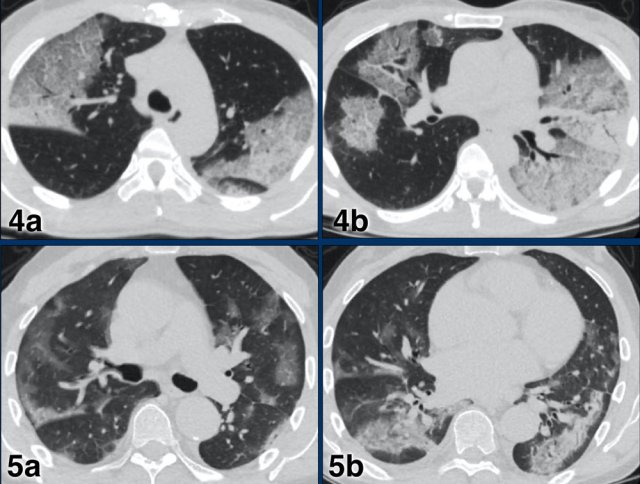

CO-RADS 5 CO-RADS 5

CORADS 5

Case 1

Multifocal GGO and consolidation

Case 2

10 days of complaints.

CT: bilateral multifocal GGO, vascular thickening (circle), subpleural bands (arrow).

PCR: positive

Case 3

Eleven days of complaints

CT findings: Bilateral GGO and consilidation, basal preference, vascular thickening (circle).

Case 4

CT findings: multifocal areas of groundglass and consolidation

Case 5